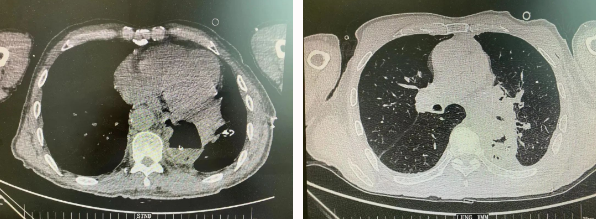

近日,胸科醫(yī)院執(zhí)行院長李小飛教授帶領胸外科一病區(qū)團隊完成一臺復雜胸外科手術:食管癌與肺癌同期手術。

患者王某不幸同時患食管癌與左肺癌,病理類型系雙源發(fā)腫瘤,食管為鱗癌、肺為腺癌。食管癌和肺癌為胸外科最常見的疾病,但同時患兩種疾病,十分罕見。家屬輾轉多個醫(yī)院,得知李小飛院長擅長胸外科復雜手術,慕名來西安國際醫(yī)學中心醫(yī)院。

經(jīng)過李小飛教授、李文海副教授、穆強副主任醫(yī)師團隊積極準備,排除手術禁忌;經(jīng)過全科術前充分討論,大家認為:如果分兩次進行手術,另一種疾病勢必會受到影響,腫瘤可能進展。胸外科手術對呼吸循環(huán)影響較大,同期實施兩個手術更要小心謹慎。李小飛教授主持術前討論,設計合理手術方式,由于食管癌胸腔鏡手術為右側入路,但為兼顧左肺癌手術,則采用傳統(tǒng)左開胸手術。

2022年4月25日,由李小飛教授主刀,同期行左側開胸:食管癌根治術 左肺癌根治術,一次手術同時根治兩種惡性腫瘤疾病。經(jīng)過精細手術及術后管理,患者術后十天,恢復良好,進食良好,現(xiàn)已出院。